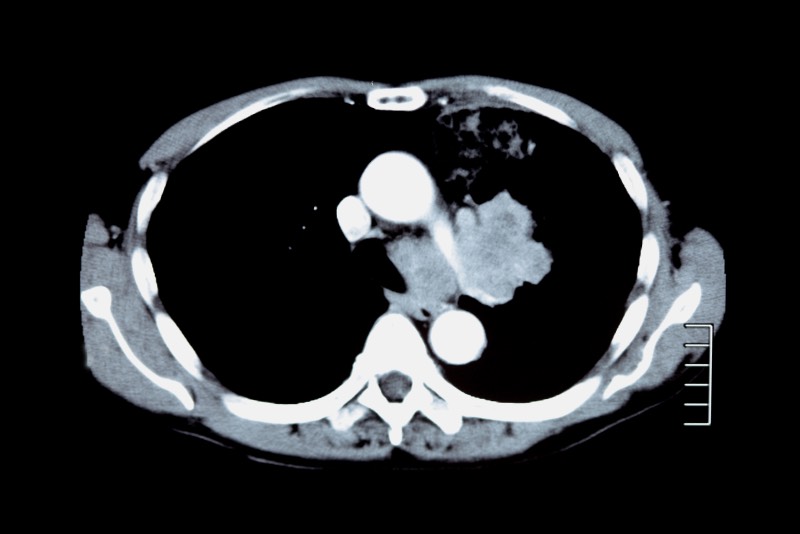

CTとは、360度回転しながらX線を照射して、コンピューターで画像処理することで、輪切りにしたような断面図や3次元の画像が得られるものです。肺、腹部などの診断に用いられるほか、実際には見えない骨の裏側や細部まで診断することができます。

当院で導入した16スライスのマルチスライスCTは、1回で16枚もの断層画像を撮影でき、より的確な画像診断が行えます。検査時間も短縮され、被ばく量も低減しています。